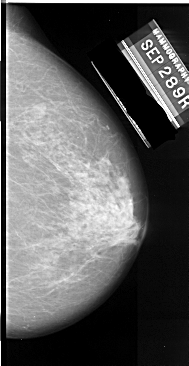

A_1065_1.RIGHT_MLO

RIGHT_MLO LINES 5476 PIXELS_PER_LINE 3181 BITS_PER_PIXEL 16 RESOLUTION 42 NON_OVERLAY